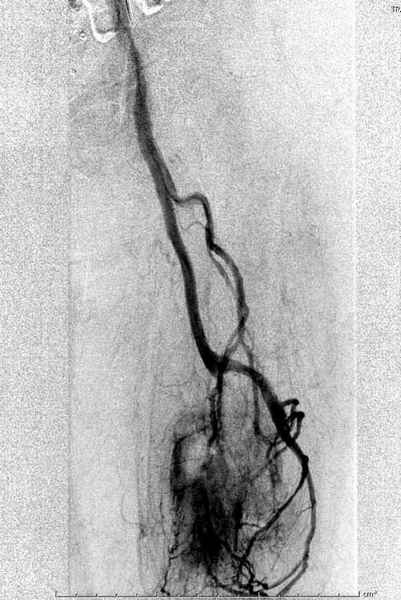

Для предупреждения кровотечения во время рассверливания, за день до операции провели эмболизацию сосудов питающий метастаз. http://radiology.rsnajnls.org/cgi/reprint/150/3/673.pdf (7-11, 12-15-16)